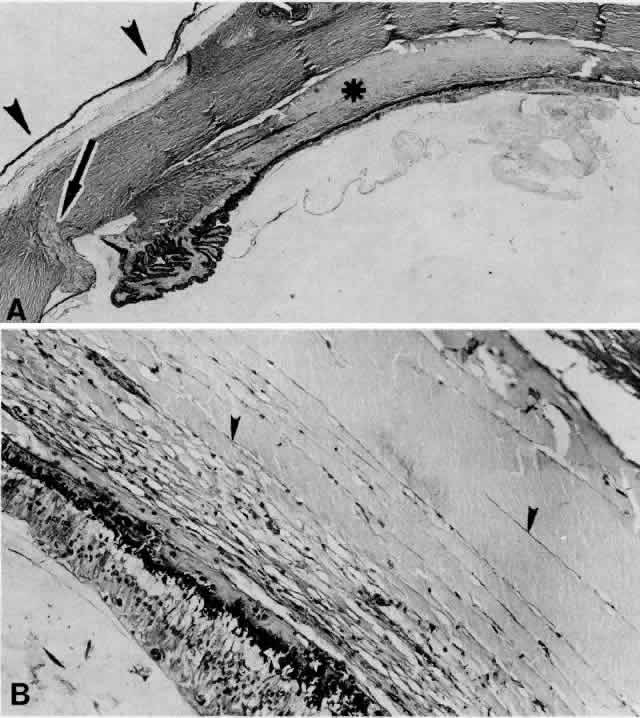

Fig. 20. A 61-year-old man presented with a 10-day history of decreasing vision in the left eye.96 Examination disclosed a vision of hand motions, an irregularly shallow anterior chamber, closure of the angle, and an intraocular pressure of 45 mmHg. The ora serrata was visible without scleral depression. Ophthalmoscopic examination disclosed two large areas of solid-appearing lesions of the pars plana and anterior choroid (situated superonasally and inferotemporally), detachment of the retina, and a diffuse pigmentary disturbance, which was linear in some areas. Transscleral transillumination disclosed that areas of solid choroidal lesions lit up when viewed through the pupil. Radioactive phosphorus uptake was 16% at 1 hour, 18% at 24 hours, and 44% at 72 hours. The eye was enucleated because of the suspicion of a malignant melanoma. A. An extensive ciliochoroidal effusion (asterisks) showing mild diffuse and marked focal (arrowhead) infiltration of lymphocytes. The equatorial sclera is markedly thickened, and there is a large serous detachment of the retina (H & E, × 17). B. Edematous choroid with a large aggregate of lymphocytes (H & E, × 100). C. The equatorial area shows a thickened sclera, an edematous choroid with diffuse and marked focal aggregates of lymphocytes, localized area of retinal pigment epithelial hypertrophy and hyperplasia (arrowheads), slight folds in the retinal pigment epithelium and inner aspect of the choroid (arrows), and proteinaceous material (asterisk) in the subretinal space (H & E, × 40). D. A choroidal effusion with overlying proliferation of retinal pigment epithelium in nodular and linear configurations. Proteinaceous material is present in some areas in or beneath the retinal pigment epithelium (arrowheads) (H & E, × 180).

Histopathologically, there is a variable lymphocytic infiltrate in the ciliary body and choroid (see Figs. 19 and 20; Fig. 21).96